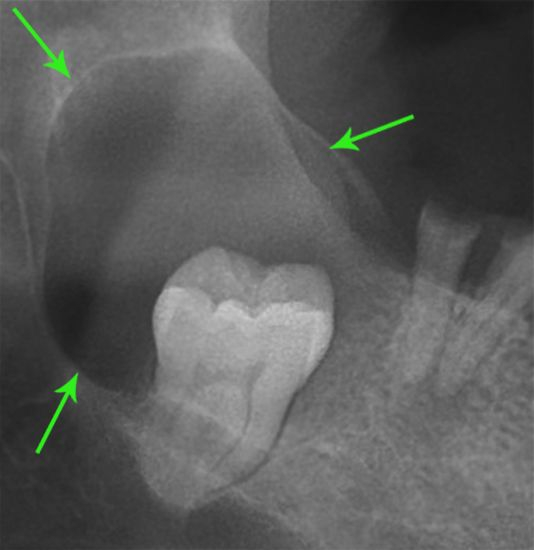

Ретинированные- те, которые сидят полностью в кости

После того, как мы сделали анестезию, мы по необходимости производим разрез и отслаиваем слизистую оболочку с надкостницей от кости (слизисто-надкостничный лоскут) и бормашиной с водяным охлаждением выпиливаем костную стенку. Почему по необходимости? Потому что эти этапы зависят от степени прорезанности и расположения зуба. Чем более прорезан зуб, тем меньше разрез и меньше убираем кости. Иногда обходимся одним разрезом, иногда даже разрез не приходится делать, а просто распиливаем зуб. Короче, смотрим по ситуации.

По необходимости распиливаем сам зуб. Опять по необходимости? Конечно! Ведь надо смотреть по ситуации и соблюдать баланс между травматичностью и скоростью проведения операции. Если зуб лежит только под слизистой, корни сросшиеся и его можно достать элеватором, то не надо лишний раз его пилить. Достали, зашили и отпустили домой. Если же у нас зуб лежит криво и достать него просто так не получается, то тогда уже пилим либо зуб, либо подпиливаем кость.

Если у зуба растопырены корни, то их тоже надо разделять и по одному доставать, как в 30 главе.